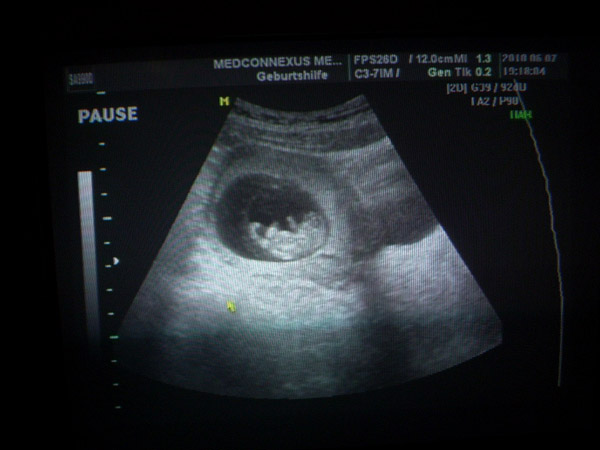

Holnap viszem húgomat első nódokilátogatáshoz Dr. Zsiraihoz/jó UH-s, 4D is csinál/ majd én is bejelentkezem és megnézetem a babóm, meg levetetem a citológiát/rákszűrést hogy ne a kollegámmal kelljen majd.